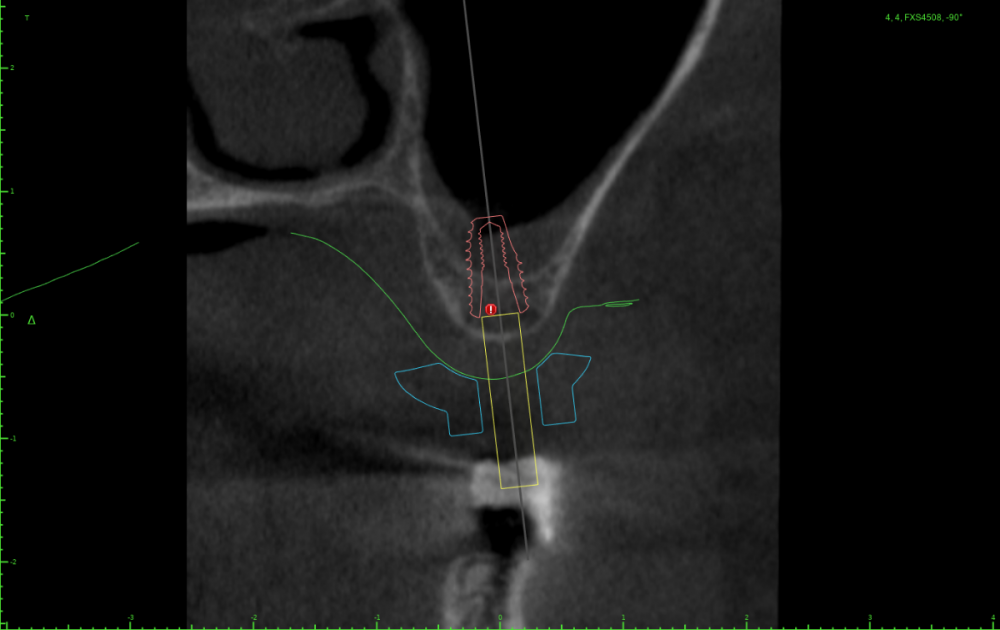

Женька Опубликовано 24 июля, 2023 Поделиться Опубликовано 24 июля, 2023 Тема ради одной фотки конечно, но всё-таки вопрос есть. Говорят МСТ профайлер не задевает стенки имплантата. Кмк, всё-таки задевает. Или всё-таки кажется? По кейсу: 2 имплантата, оба по шаблону. Черт дёрнул пройти глубже чем планировал в 1.6, фрезой перфо не создал, но кортикалку в ноль убрал. И при отслойке всё-таки порвал немного. Тампонировал губками, пробы отрицательные. Вроде нигде не перемудрил в этот раз, @АнтонТЛТ ? 3 Ссылка на комментарий

АнтонТЛТ Опубликовано 25 июля, 2023 Поделиться Опубликовано 25 июля, 2023 Значит пора выложить скрины проекта шаблона) посмотреть что там с параллельностью, если там всё параллельно, тогда искать причину почему имплантаты завалены Ссылка на комментарий

Женька Опубликовано 25 июля, 2023 Автор Поделиться Опубликовано 25 июля, 2023 23 часа назад, Женька сказал: Но буду честен, можно было чутка 1.4 наклонить и сооснопоставить. я же уже говорил об этом. Вот если бы параллелил по 1.6 . Как по мне так себе позиция Поэтому выбрана такая И соответственно если бы параллелил по 1.4 Ссылка на комментарий

АнтонТЛТ Опубликовано 25 июля, 2023 Поделиться Опубликовано 25 июля, 2023 А сагиттальный срез? Ссылка на комментарий

АнтонТЛТ Опубликовано 25 июля, 2023 Поделиться Опубликовано 25 июля, 2023 По фото выглядит так как будто установлены так Ссылка на комментарий

АнтонТЛТ Опубликовано 25 июля, 2023 Поделиться Опубликовано 25 июля, 2023 Кт не делали после установки? Интересно было бы подгрузить к новому снимку stl скана+шаблона+имплантатов Ссылка на комментарий

Женька Опубликовано 26 июля, 2023 Автор Поделиться Опубликовано 26 июля, 2023 (изменено) @АнтонТЛТ , не, не делали. Через полгодика сделаю, как раз пластика с другой стороны (сетка, которую выкладывал) должна созреть.) Возможно из-за синуса ось сместилась ну и были определённые проблемы привязки КТ и скана. Зубы есть, но программа не хотела даже по точкам сопоставлять. Пришлось в ручную. саггиталь не могу выстроить как не кручу, чтобы оба болта попали. Изменено 26 июля, 2023 пользователем Женька Ссылка на комментарий